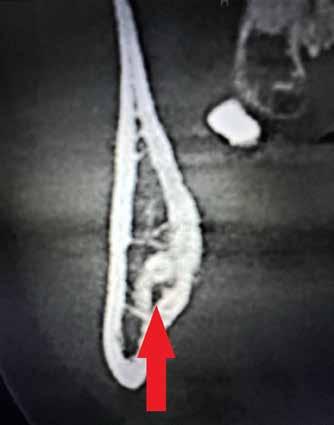

A CT metszetekben a 48-as gyökerei körbeölelik a canalis mandibularist, amelyet piros nyíllal jelöltünk a fotókon.

rációval tudom felszabadítani a koronát, másrészt, hogy a gyökerek 1-2 mm-nél ne kerüljenek közelebb a canalishoz. A fejlődési ütemüket követve, előreláthatólag kb. 15-16 éves korukra érik el a fogaik ezt az állapotot.

Szeretnék mutatni néhány ábrát az egyik bonyolult esetről, a közelmúltból. A CT-n látszik, hogy a három gyökér teljesen „körbenőtte” az ideget. Van olyan frontális metszeti kép, ahol csak a gyökerek vannak a nervus körül, ezen a szakaszon egyáltalán nincs meg a csontos fala a canalisnak. Szeparációs technikával, viszonylag könnyen, minimális traumával, szövődménymentesen sikerült eltávolítani a fog minden részét. A várakozásnak megfelelően, a beteg nem számolt be paraesthesiáról.

Alapos kivizsgálással, részletes tervezéssel, óvatos műtéti technikával még ilyen, extrém esetekben is sikeresen, szövődménymentesen meg lehet oldani a komplikált helyzeteket. Jobb lenne azonban, ha a műtét időpontjának helyes megválasztásával elkerülhetőek lennének ezek a magas rizikójú beavatkozások.